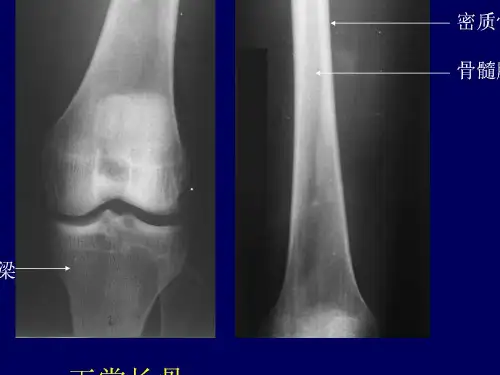

与儿童相比,外形相似,骺与 干融合,骺板消失。两侧形成骨 端,两端有关节面,关节面被覆 透X线的关节软骨。